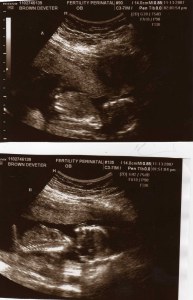

When I looked at the sonogram screen I was not expecting to see two little blips. One floating ever so gently (Leah Twin A) and the other ‘jumping’ up and down (Myles Twin B). I even asked the technician NOT to tell me that I was having twins. So she didn’t

, instead she called my wonderful husband and 3 year old son into the room; congratulated them and told them we would go from a family of three to a family of five! My beautiful husband said cool! See I was sick the ENTIRE time. From the moment I realized we were pregnant I was SICK. Not morning sickness, ALL DAY sickness. Couldn’t eat, couldn’t drink ugh it was awful! So hearing that we were having twins was an answer for him, to the question “why are you so sick”. I on the other hand, I sat in a daze for about two weeks. Yes, I was in a daze for two weeks. Me with twins? How did that happen???